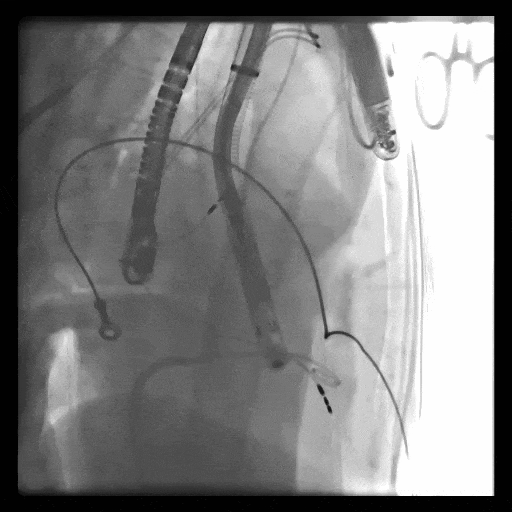

第一例患者手術(shù)難點

1、血管入路問題,最窄處平均徑5.5mm(小于8.5mm),輸送器存在進入受阻礙風(fēng)險; 2、投照體位過大,RAO76°,術(shù)中影響輸送器操作可能性大;3、三尖瓣環(huán)大,同軸性難調(diào)整,易產(chǎn)生瓣周漏;4、起搏器導(dǎo)線在三尖瓣瓣環(huán)中心位置穿過,且較短,可能限制人工瓣膜展開,且尖端靠近室間隔錨定區(qū),可能影響錨定;5、三尖瓣極重度反流,藥物不能緩解患者的癥狀,在應(yīng)用LuX-Valve Plus之前,心臟專家經(jīng)長時間評估均未為患者找到合適的產(chǎn)品或治療方案。

術(shù)中DSA顯示起搏器導(dǎo)線的干擾,右心室造影確定瓣環(huán)位置,操作空間小